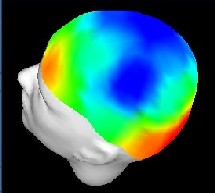

Mapa del cerebro humano